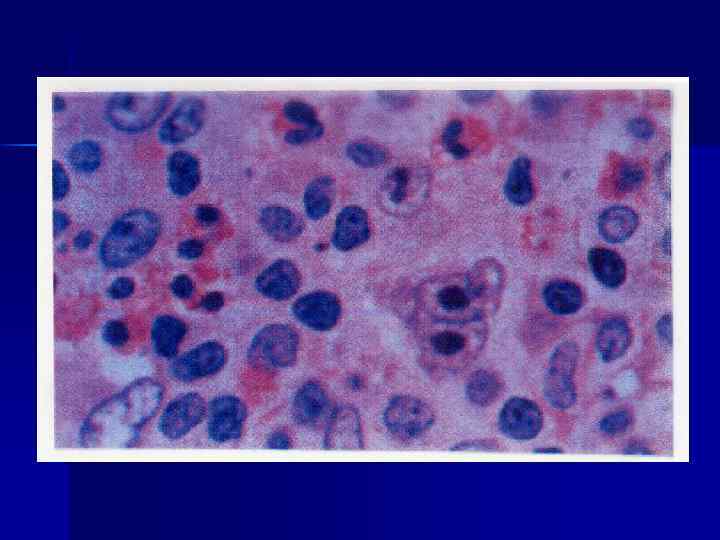

Микропрепараты: Лимфогранулематоз и Нодулярный Склероз

Раздел: Секреты мастерства